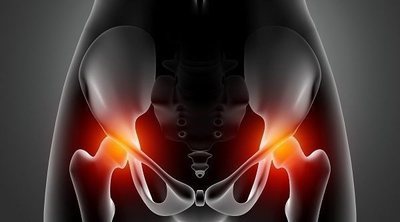

Signos claros de una fractura de cadera

A partir de una cierta edad los huesos se vuelven más débiles pudiendo favorecer ciertas fracturas como es el caso de la cadera.